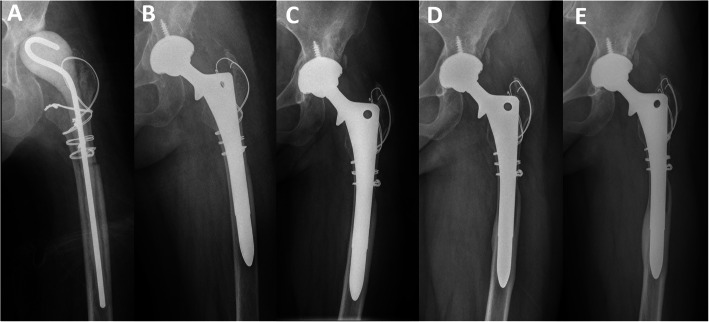

Fig. 1.

Anteroposterior radiographs of a 48-year-old woman who underwent revision THA for periprosthetic joint infection. a Radiograph prior to stage 2 revision THA showing the antibiotic-loaded spacer in situ. b Radiograph immediately after revision THA using a cementless extensively porous-coated stem without cortical strut allografts. c Postoperative radiograph at 1 year showing loss of cortical density and thickness in the proximal femur, suggesting moderate area and severity of stress shielding. d Postoperative radiograph at 5 years showing severe stress shielding and distal cortical hypertrophy on both the medial and lateral sides. e Postoperative radiograph at 10 years showing more severe bone loss and distal cortical hypertrophy